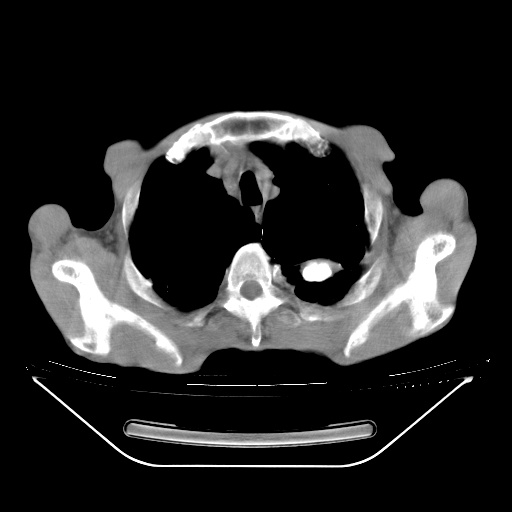

以下是引用zsl6918在2008-8-25 21:55:00的发言:[br]符合右肺周围性肺癌并肺内转移,左肺结核球。双肺肺气肿。腰椎附件转移。

以下是引用随光逐影在2008-8-25 22:03:00的发言:[br]1)考虑右肺下叶周围性肺癌并肺内转移,腰椎附件转移。2)左上肺结核(结核球形成)。3)双肺肺气肿(多发肺大泡形成)。4)双肺门区及纵隔内多发淋巴结钙化。